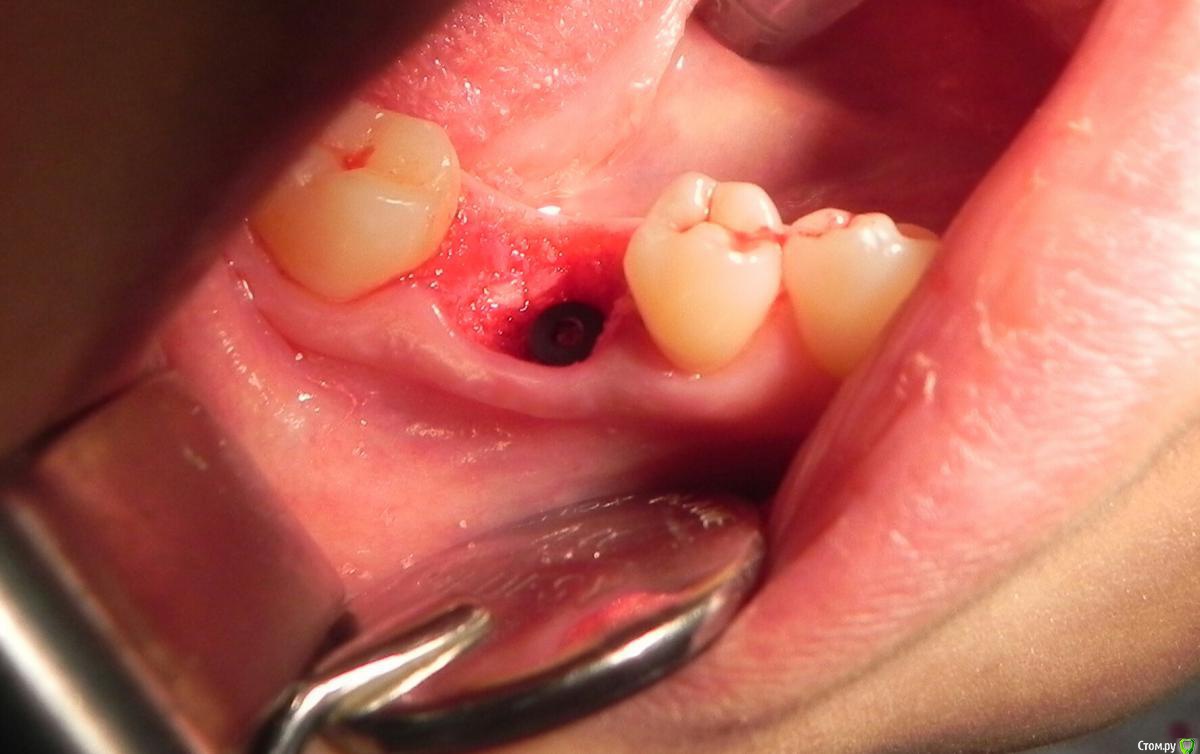

Kostoprav Опубликовано 24 мая, 2016 Поделиться Опубликовано 24 мая, 2016 удалил, вкрутил,графт gen oss, фдм.P.S. сори за плагиат) 3 Ссылка на комментарий

red_butler Опубликовано 25 мая, 2016 Поделиться Опубликовано 25 мая, 2016 Я бы в данном случае, обошелся бы без графта. 2 Ссылка на комментарий